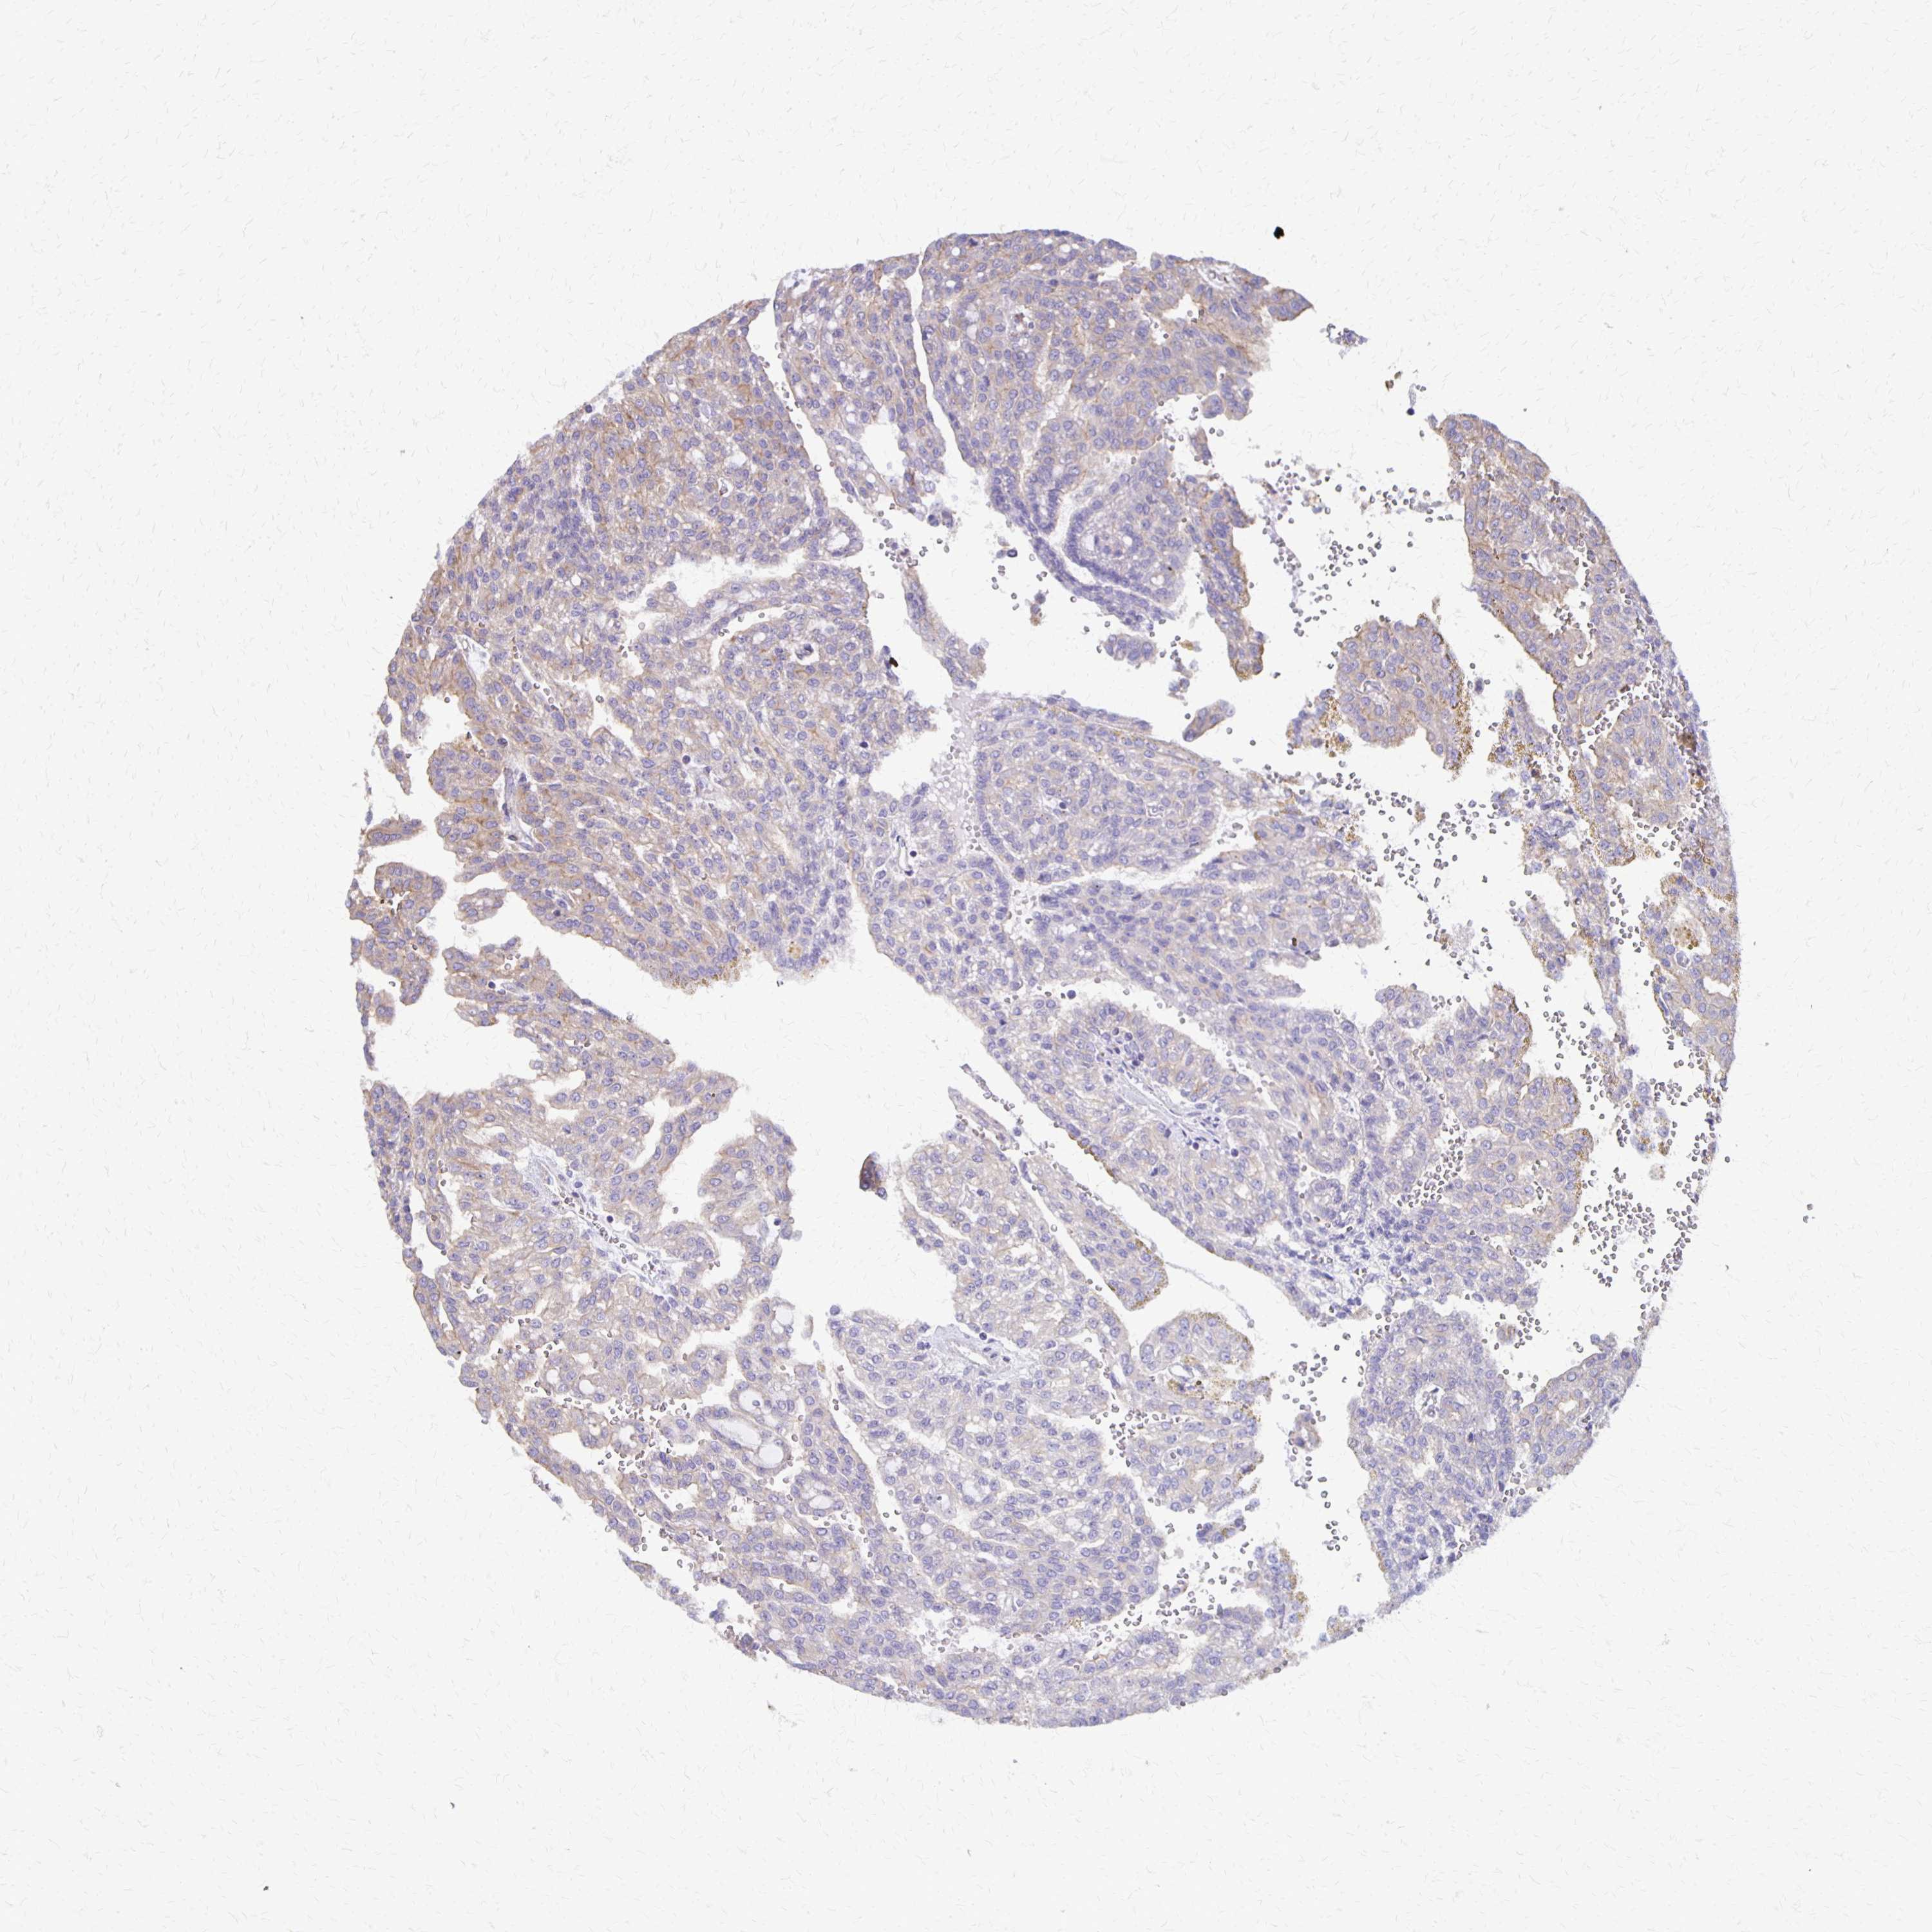

KIDNEY RENAL PAPILLARY CELL CARCINOMA (TCGA) - Interactive survival scatter ploti

The Survival Scatter plot shows the clinical status (i.e. dead or alive) for all individuals in the patient cohort, based on the same data that underlies the corresponding Kaplan-Meier plots. Patients that are alive at last time for follow-up are shown in blue and patients who have died during the study are shown in red.

The x-axis shows the expression levels (FPKM) of the investigated gene in the tumor tissue at the time of diagnosis. The y-axis shows the follow-up time after diagnosis (years). Both axes are complimented with kernel density curves demonstrating the data density over the axes. The top density plot shows the expression levels (FPKM) distribution among dead (red) and alive patients (blue). The right density plot shows the data density of the survived years of dead patients with high and low expression levels respectively, stratified using the cutoff indicated by the vertical dashed line through the Survival Scatter plot. This cutoff is automatically defined based on the FPKM cutoff that minimizes the p-score. The cutoff can be changed by dragging the vertical line or by entering a cutoff value in the square labeled "Current cut-off".

Under the Survival Scatter plot the p-score landscape (black curve; left axis) is shown together with dead median separation (red curve; right axis). Dead median separation is the difference in median mRNA expression between patients who have died with high and low expression, respectively. It is calculated as follows: median FPKM expression of dead patients with high expression - median FPKM expression of dead patients with low expression. This is intended to aid the user in visually exploring custom cutoffs and the associated p-scores and dead median separation.

Individual patient data is displayed and can be filtered by clicking on one or more of the category buttons on the top of the page. Categories describing expression level and patient information include: high, low, alive, dead, female, male and tumor stages. The scale of the x-axis can be toggled between linear and log-scale by clicking on the "x log" button. Mouse-over function shows TCGA ID, patient information and mRNA expression (FPKM) for each patient.

& Survival analysisi

Kaplan-Meier plots summarize results from analysis of correlation between mRNA expression level and patient survival. Patients were divided based on level of expression into one of the two groups "low" (under cut off) or "high" (over cut off). X-axis shows time for survival (years) and y-axis shows the probability of survival, where 1.0 corresponds to 100 percent.

SEPTIN5 is not prognostic in Kidney Renal Papillary Cell Carcinoma (TCGA)

Best expression cut offi

Based on the FPKM value of each gene, patients were classified into two groups and association between prognosis (survival) and gene expression (FPKM) was examined. The best expression cut-off refers the FPKM value that yields maximal difference with regard to survival between the two groups at the lowest log-rank P-value. Best expression cut-off was selected based on survival analysis .

When clicking on this number, the vertical dashed line indicating cut-off, the interactive survival plot, and the Kaplan-Meier curve will be adjusted to show results based on the best expression cut-off.

: 3.92